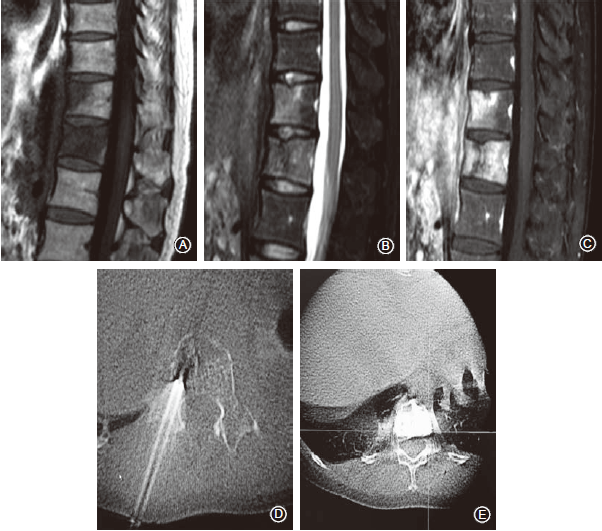

四、影像学评价结果

随访期间影像学复查93.75%(30/32)的患者靶椎控制良好(图3,4);2例(6.25%)患者在术后6个月出现局部病灶进展,临床出现局部疼痛加重并需要止痛药物维持。

此2例分别为乳腺癌和肺癌各1例,肿瘤瘤体直径>2cm且有椎旁软组织肿块等因素与局部进展有关。1例乳腺癌T11转移患者原发肿瘤治疗有效,局部肿瘤进展未引起脊髓压迫症状,该例患者密切随访观察中;另1例肺癌患者局部进展接受外照射治疗。